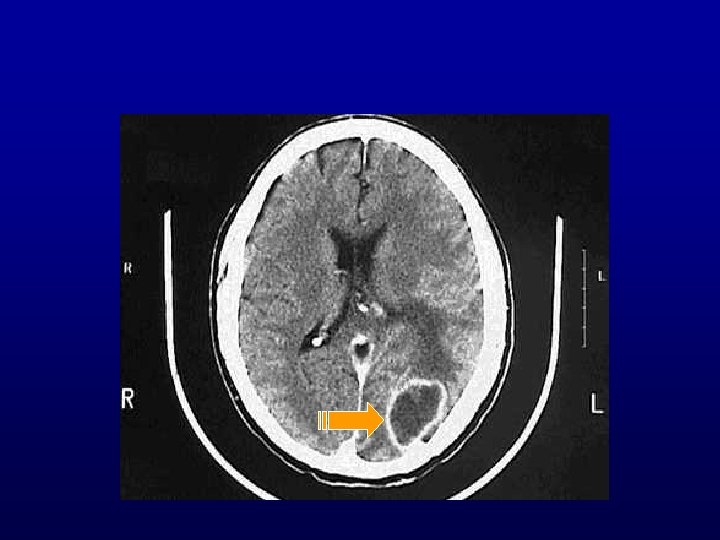

Brain Abscess • Bacterial and fungal organisms • Sources of brain abscesses – Otogenous (temporal lobe or cerebellar) – Rhinogenic (paranasal sinuses) – Traumatic (e. g. , stab wound) – Metastatic, hematogenously spread from • Bacterial endocarditis, septicemia • Lung abscess or bronchiectasis • Intestinal flora in congenital heart disease with a right to left shunt • Osteomyelitis

Pathogenesis of brain abscess • Preexisting necrosis: – Direct extension from adjacent focus (thrombophlebitis venous infarct) – Infected emboli (occlusion of a small artery or arteriole arterial infarct) • Necrosis leads to frank suppuration • After a week or two, a fibrous wall (derived from the vasculature) that may be several mm thick after 4 -5 weeks forms • Outside the fibrous wall, there are perivascular, chronic inflammatory cells and white matter edema (perifocal edema) • An intense astrocytic gliosis takes place with formation of a glial scar

• Location • Mastoiditis temporal lobe or cerebellar abscess • Frontal sinusitis and ethmoiditis frontal lobe abscess • Metastatic (hematogenously derived) abscesses anywhere Disseminated (metastatic) microabscesses are usually due to sepsis or acute bacterial endocarditis, and are multiple • Common organisms are Staph, Candida, and anaerobes (Bacterioides Fragilis) • Patients always have underlying immunosuppression

Complications of brain abscesses • Destruction of vital centers (e. g. , medulla oblongata) • Rupture of the abscess causes empyema: – Meninges (leptomeningitis) – Ventricles (ventriculitis) • Increased intracranial pressure, due to: – Mass effect from large abscess – Perifocal inflammatory edema

Pathogenesis&Complications Necrosis Supuration Fibrous wall Empyema Gliosis Perifocal edema Mass effect Intracranial pressure

BRAIN ABSCESS